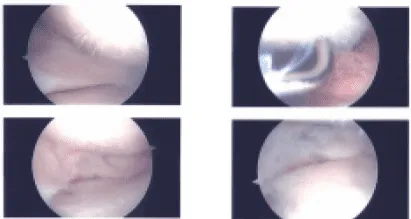

Imágenes intraoperatorias

Se insertó un artroscopio. Se realizó un portal de acceso médico con el uso de una aguja espinal. El examen del compartimento tibiofemoral medial mostró una ruptura del menisco medial en el cuerno posterior. También mostró lesiones osteoartríticas de grado 3 a 4 en la meseta tibial medial, así como cóndilo femoral.

El desbridamiento del menisco medial se realizó con afeitadora y mordedores. También se realizaba desbridamiento del cartílago y se realizaba condroplastia con el uso de una afeitadora. El examen de la muesca intercondilar mostró LCA intacto.

El examen del compartimento tibiofemoral lateral mostró cartílago y menisco intactos. El examen del compartimento patelofemoral mostró troclea intacta, pero lesión osteoartrólica de grado 2 a grado 3 del cartílago rotuliano.

El desbridamiento se realizaba mediante una afeitadora. Se insertó el artroscopio a través del portal de entrada medial y se redujo el afeitador desde el portal de entrada lateral para equilibrar aún más el menisco medial. Se tomaron y guardaron las fotos finales.